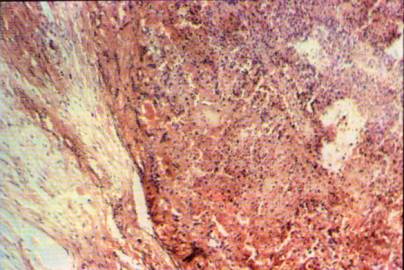

Foto 27: Marcada necrobiosis tumoral, periferia constituida por estroma neovascular típico ya descrito <H.E.>.

Foto 28: Áreas hemorrágicas con afluencia de leucocitos Polimorfonucleares piocitarios<H.E.>.

Foto

29: Sectores de intensas atipías celulares con elementos multinucleados (M)

. Extensas áreas del

tejido neoplásico estudiadas a menor aumento mostraron necrosis, hemorragias

con depósitos de hemosiderina, septos fibrosos intratumorales, trombosis

vasculares y borramientos masivos de la estructura debidos a isquemia (foto 27).

Pudiendo considerarse viable solo un 20% de la masa extirpada pues el

resto se constituye de áreas necróticas, hemorragias y fibrosis reparativas.

Las áreas necróticas muestran la presencia de infiltrado

polimorfonuclear neutrofilico en degeneración piocitaria (foto 28), además de

extensos sectores hemorrágicos.

Las células que conforman la neoplasia no muestran universalmente la

apariencia habitual de células claras, monótonas y bien organizadas, sino que

presentan numerosas áreas de intensa atipía con anisocariosis marcada,

multinucleación, nucleolos múltiples, índice mitótico elevado, mitosis atípicas

y tendencia a la necrosis aún en áreas próximas a estructuvasculares (foto

29).

Los cambios fueron tan llamativos que recuerdan a los observados en las

biopsias de pacientes tratados con quimioterapia o radioterapia; dejándose

constancia que en este caso no hubo tales terapéuticas a nivel del área

biopsiada, solamente se efectuó radioterapia craneana total.

Los cambios morfológicos de las células tumorales no aparecen como

secundarios al proceso reactivo, dado que las atipías se observan aún en

sectores viables del tumor. Es

interesante destacar que el área de contacto entre el estroma y el tumor se

halla constituida por un substrato de elementos fibroblásticos jóvenes y

neovasculares con la presencia de un infiltrado linfocitario con escasos

plasmocitos que se disponen a lo largo de la línea de choque a modo de barrera

(foto 30).

30: Disposición característica en barrera del infiltrado de macrófagos y células

"T" (1)